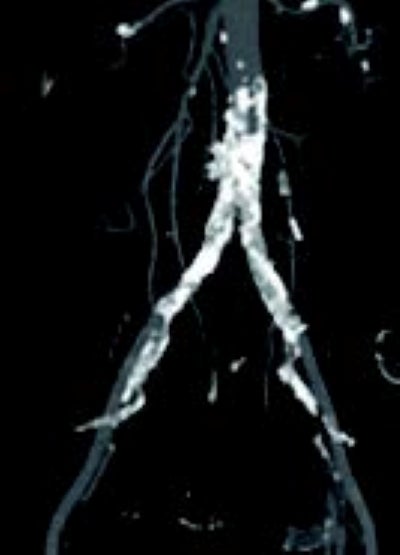

術前のCT(図1)と下肢造影(図2)より、大動脈遠位端の偏心性石灰化狭窄、右総腸骨動脈(CIA)の石灰化狭窄、左CIAの石灰化亜閉塞を認めた。大動脈からCIAの石灰化病変は連続しており、大動脈から両側CIAにかけてのキッシングステントが望ましいと判断した。腰痛が強く、術後安静が困難であるため両側橈骨動脈アプローチとした。

両側橈骨動脈より順行性に両側CIAにガイドワイヤーを通過させた。病変は偏心性石灰化でバルーン拡張により血管破裂のリスクがあることからVBXステントグラフト7.0 × 79 mm(6 Fr)を選択した。両側橈骨動脈からのアプローチにより(図4)スコアリングバルーンによる前拡張後(図5,6)、VBXステントグラフトを留置し(図4,7)、後拡張として高耐圧バルーン8.0 × 40 mmでキッシングバルーンテクニック(KBT)を行った(図8)。この際に迷走神経反射により心拍数が39回/分となったことから、これ以上の径での拡張は危険と判断し、手技を終了した。VBXステントグラフト留置後(図9)と術後造影(図3)では良好な血流が確認された。

足関節上腕血圧比(ABI)は術前は右0.97左0.61が、術後は右1.15左1.11へと改善が確認された。